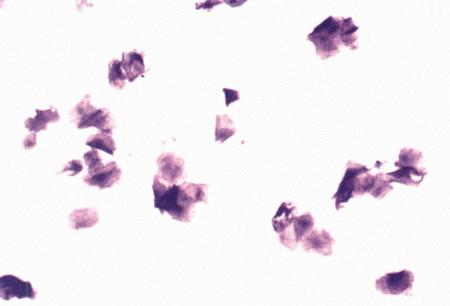

Вагинальная цитология

Повышение концентрации эстрадиола в период проэструса стимулирует деление клеток в базальных слоях вагинального эпителия, но затем концентрация эстрадиола, а соответственно и эндокринная поддержка образования нового, многослойного эпителия снижается, поэтому в образце обнаруживается больше мертвых ороговевших клеток. По мере развития проэструса снижается количество эпителиальных клеток, содержащих ядро. С начала до середины проэструса в вагинальных мазках обнаруживают повышенное содержание эритроцитов. Пик ороговения совпадает с началом повышения концентрации прогестерона; однако в начале эструса исследование не обнаруживает характерных особенностей, которые могли бы указывать на начало фертильного периода. Как правило, такой период наступает несколькими днями позже (табл. 1.1). Тем не менее вагинальная цитология остается популярным методом определения репродуктивного статуса суки из-за своей дешевизны, простоты и доступности. Для получения образца используют ватный тампон, предпочтительно небольшой, который вводят во влагалище и осторожно берут мазок. Полученные клетки помещают под микроскоп, а затем окрашивают контрастным (трихромом) или неконтрастным (например, препаратом Diff-Quik) веществом. При таком окрашивании мертвые кератинизированные клетки становятся оранжевыми, тогда как активные ядерные клетки, а также базальные и парабазальные эпителиальные клетки приобретают различные оттенки от голубого до зеленого.

Ближе к окончанию эструса вагинальные выделения претерпевают характерные изменения (снова выявляются эпителиальные клетки, содержащие ядро, и появляется большое количество лейкоцитов). Такая картина обычно наблюдается через 7–9 дней после пика ЛГ и известна как «вагинальный мазок метэструса». Изменению характера выделений предшествует переходный период, характеризующийся возрастающим количеством активных клеток и указывающий на окончание фертильного периода и эструса (табл. 1.1).

Вагинальная цитология весьма информативна в плане определения фазы эстрального цикла, однако значительные расхождения во времени появления основных признаков эструса по отношению к пику фертильности ограничивает применение указанной методики.

Фиг. 2.2.

Вагинальные выделения кошки (а). Выделения, типичные для фазы эструса. Большая часть клеток представляет собой безъядерные кератинизированные клетки или клетки с пикнотическим ядром. Присутствуют промежуточные клетки (b). Выделения, характерные для метэструса, — «течки», иногда наблюдаемой у кошек в конце эструса. Присутствуют поверхностные и промежуточные клетки, повышено содержание лейкоцитов. Этот короткий метэструс наблюдается в течение 24–48 часов (см. Приложение)